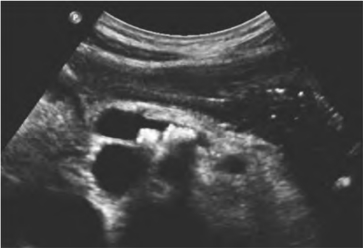

(2)胰管可扩张,表现为胰管管径增大之条状液性暗区或多个串珠样相连之液性暗区。扩张的胰管内如有结石可见强光团回声,其后有声影(图26-7)。

图26-7 慢性胰腺炎伴胰管结石声像图